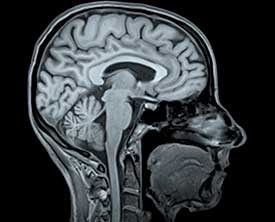

Способы диагностики

Ключевыми методами для проведения диагностического обследования являются:

- Магнитно-резонансная томография (МРТ).

- Рэоэнцефалография (РЭГ).

- Ультразвуковая доплерография.

- Ангиография.

Данные процедуры назначаются в зависимости от результатов осмотра пациента и истории болезни.

Как диагностируется тромб в голове?

Диагностика тромба в голове обычно включает нейровизуализацию, такую как компьютерная томография (КТ) или магнитно-резонансная томография (МРТ), которые помогают выявить наличие тромба и оценить состояние мозга. Также могут быть проведены анализы крови для определения факторов риска.